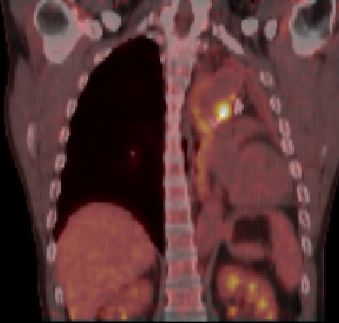

| PET-CT | 60jähriger Mann 18 Monate nach Pneumektomie links wegen Plattenepithelkarzinom des linken Lungenoberlappens pT2a pNo Mo![]() ![]() |